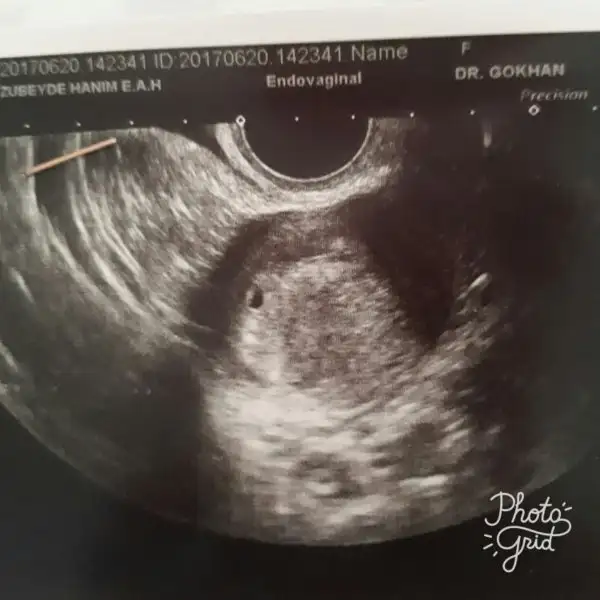

Canım orda bir kese gorunüyor. Göruntüyu buyutseydi daha net gorurdun. Doktorun keseyi ölcmedi mi. Genelde beta hcg 1000 in üstüne çiktiginda doktorlar bakmak istiyor. Daha rahat gorunuyormuş. Cok erken gitmissin.Haftaya daha net anlasilacaktir. İçin rahat olsun. Insallah kalp atislarinida duyarsin bebegininEki Görüntüle 2011611 Bebeğinin kesesini gören arkadaşlar bi bakınn

Doktordan geldim çok minnak birşey var ama kese gibi sanki ama çok erken daha dedi doktor haftaya bidaha gel dedi şu fotoda görünüyor bi bakın lütfeeeennn

ayyyy minnak maşallah ya küçücük inşallah sağlıkla gelişimini tamamlar ve hayatınıza güzellikler getirerek merhaba derEki Görüntüle 2011611 Bebeğinin kesesini gören arkadaşlar bi bakınn